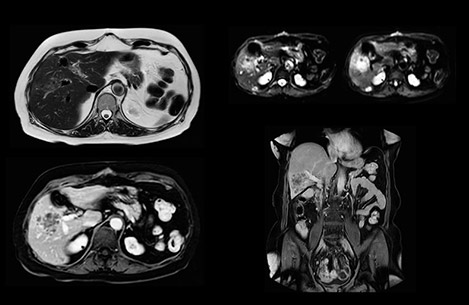

Comparison of liver MRI with and without MultiVane XD motion correction

In this example the image quality of the MultiVane XD images is evidently better than in the images without MultiVane XD. Ingenia 1.5T with dS Torso coil solution.

“We acquire one transversal high resolution T2-weighted sequence with 3 mm slice thickness, for example for pancreas or liver lesions. Then we also add a T2 fat suppressed MultiVane XD SPIR sequence. We perform these two routinely in our liver imaging. We use high dS SENSE factors to significantly shorten scan times to 2-4 minutes, which can improve our protocol; it’s a very robust scan.”

“We include mDIXON for the dynamic sequences because of the robust and homogeneous fat suppression we get with that. We had been using eTHRIVE, but we are now quite happy with mDIXON. Sometimes we use a medication to calm the bowels, to further improve the image quality.”